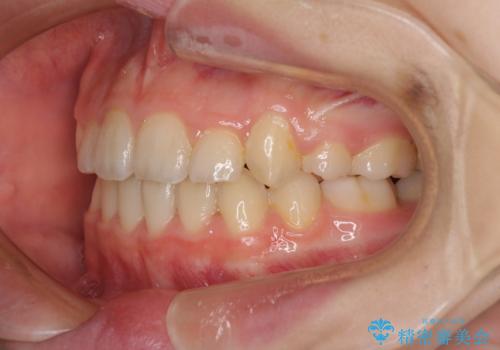

- 八重歯と乳歯が残っていることを気にして来院された患者様です。

乳歯が3歯残っており、下顎は左右ともに後続永久歯がない状態でした。

口元が突出しており、口が閉じにくかったため、乳歯を含め上下5歯を抜歯して矯正治療を行うこととしました。

下顎の乳歯は永久歯と比べて幅が大きいため、抜歯した場合のスペースが大きく、治療には長期間を要することが一般的です。

今回の患者様は中学生ということもあり、成人の患者様と比べ動きが速く、2年間で治療を終えることができました。